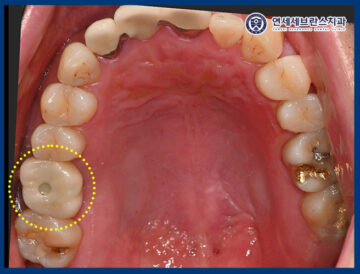

25.12.11

<맞춤형 지대주 및 크라운 제작>

이렇게 맞춤형 지대주와 크라운을

제작하여 맞춰 보았습니다.

주변 치아와의 형태와 색상,

그리고 교합 관계까지

조화롭게 어울리는 것을

확인할 수 있었습니다.

환자분께서는 타 치과에서 임플란트를 했을 때는

시간도 오래 걸리고 많이 힘들었는데

이번 재수술은 아프지도 않고

깔끔하게 끝난 느낌이라며 만족해 주셨으며,

정기검진 잘 오겠다고 해주셨습니다.